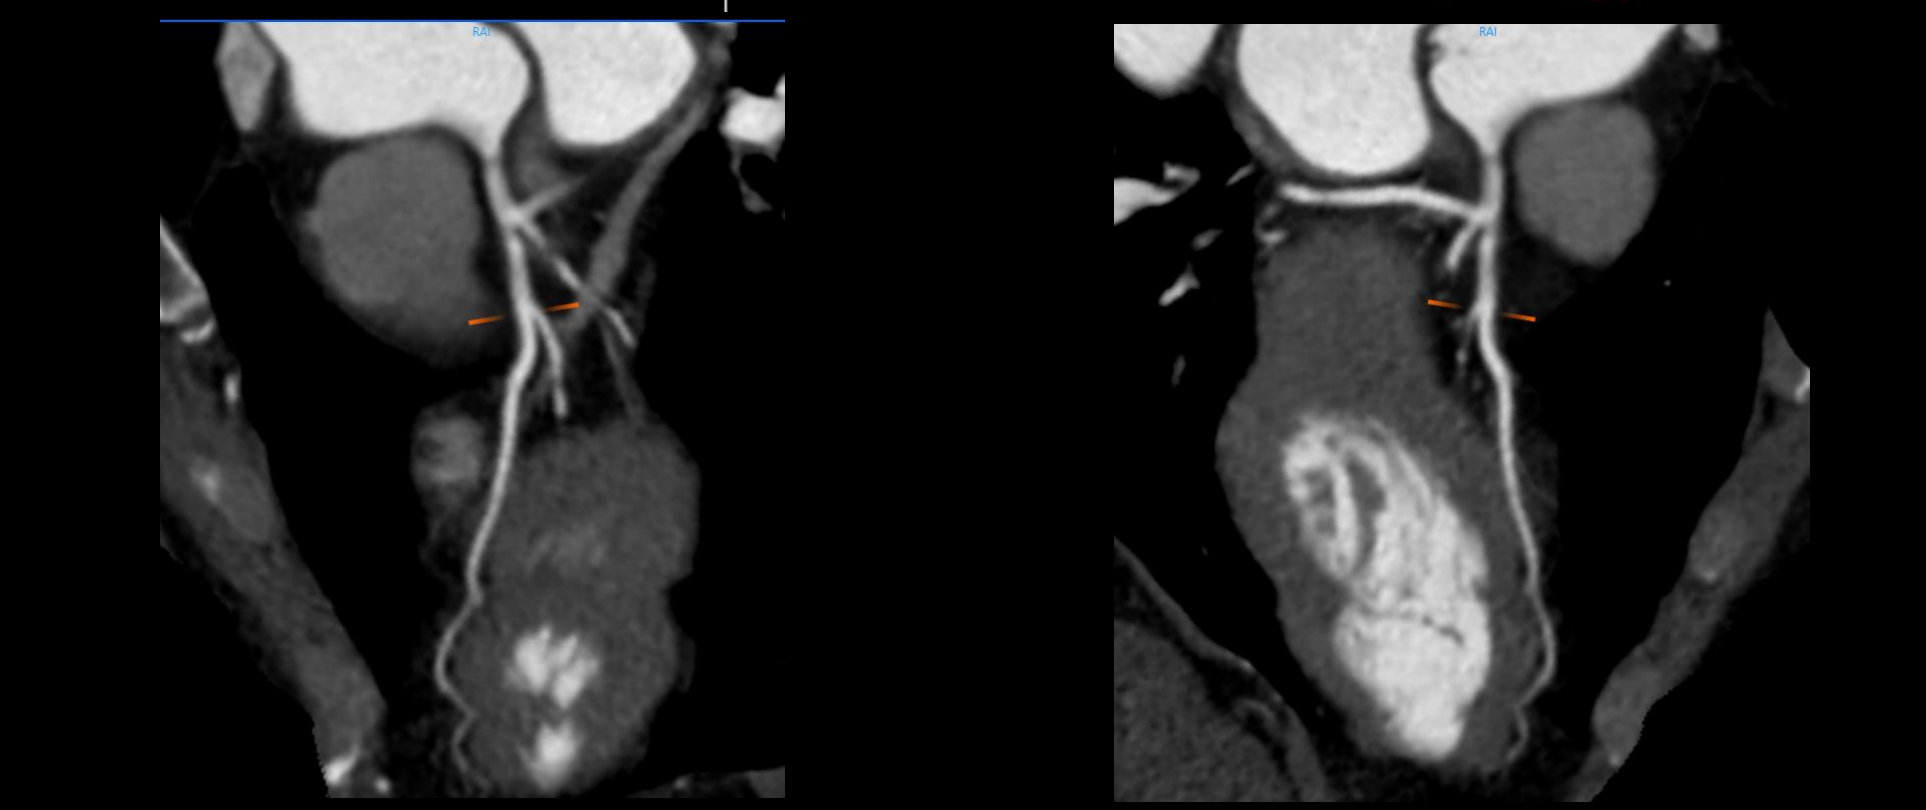

- Giải pháp chẩn đoán hình ảnh mô mềm tiên tiến cho khảo sát ổ bụng

- Tối ưu chất lượng hình ảnh chẩn đoán và giảm phơi nhiễm bức xạ

- Hỗ trợ đánh giá an toàn cho bệnh nhân

- Đảm bảo chất lượng hình ảnh chẩn đoán cao